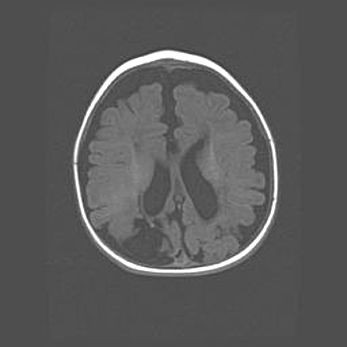

Лейкомаляция с кистозно-глиозной дегенерацией головного мозга.

Возраст: 2 месяца 25 дней

Вес: 6400 г

Окружность головы: 40 см

Срок гестации: 41 неделя

Лейкомаляцию относят к ишемически-гипоксическим повреждениям головного мозга, диагностируемым у новорожденных. При лейкомаляции в головном мозге обнаруживают очаги некроза, возникшие после тяжелой гипоксии и нарушения кровотока. В процессе морфогенеза очаги проходят три стадии: 1) развития некроза, 2) резорбции и 3) формирования глиозного рубца или кисты. Перивентрикулярная лейкомаляция (ПЛ) встречается примерно в 12% случаев среди новорожденных, обычно – у недоношенных детей, причем, частота ее зависит от массы, с которой младенец появился на свет. Наибольшее число малышей страдает лейкомаляцией, если масса при рождении 1500-2500 г.